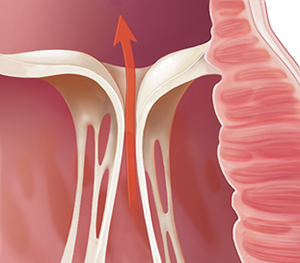

Problems closing (regurgitation)

When a valve doesn’t close tightly enough and blood leaks backward through the valve, the problem is called regurgitation or insufficiency. The valve itself may be described as leaky. Leaflets may fit together poorly. Or the structures that support them may be torn. Some blood leaks through the valve back into the chamber it just left. So the heart has to move that blood twice. This can result in heart muscle damage.

|

| Regurgitation. |